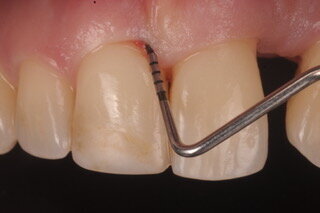

Ogni operatore odontoiatrico deve essere in grado di fare diagnosi di parodontite intercettandone i segni clinici: arrossamento delle gengive, sanguinamento al sondaggio, aumento del sondaggio parodontale, mobilità e migrazione dei denti e alitosi. È semplice farlo basandosi su uno screening detto PSR (Periodontal Screening and Recording) attraverso il quale i pazienti vengono differenziati in soggetti parodontalmente sani, con sola gengivite cioè infiammazione dei tessuti superficiali e assenza di perdita di attacco e infine soggetti con parodontite più o meno grave a seconda della profondità di sondaggio via via maggiore, nei quali l’infezione ha fatto perdere attacco parodontale conducendo alla perdita di tessuto osseo di supporto che si espleta nella formazione di difetti ossei a carico di uno o più elementi dentari.

Una volta intercettata la patologia parodontale l’operatore ha il dovere di approfondire la diagnosi compilando una cartella parodontale completa e rilevando, a seconda della distribuzione dei sondaggi, radiografie intraorali periapicali per poter valutare l’espressione della patologia a carico dei tessuti profondi; infine l’attenta anamnesi familiare e individuale permette all’odontoiatra di inquadrare i molteplici fattori di rischio eventualmente correlati (fumo, diabete familiarità, età, stress etc.).